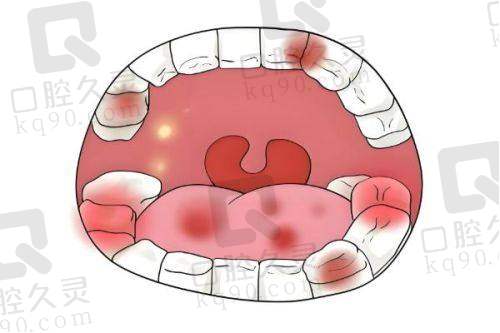

医疗团队的专精水平直接关系到医院的诊疗质量。衢州蓝芽口腔汇聚了一批经验多、技术不错的口腔医生。这些医生毕业于有名的口腔医学校校,接受过系统的专精教育。他们在口腔领域有着多年的临床实践经验,擅长处理各种口腔疾病,如龋齿、牙周炎、牙髓炎等,同时在牙齿矫正、种植牙等高端口腔项目上也有着出色的表现。此外,医院还会定期组织医生参加学术交流活动和专精培训,让他们及时了解国内外全新的口腔医学技术和理念,不断提升自身的专精水平。通过这些举措,衢州蓝芽口腔的医疗团队能够为患者提供更加优质、效率高的口腔诊疗服务。